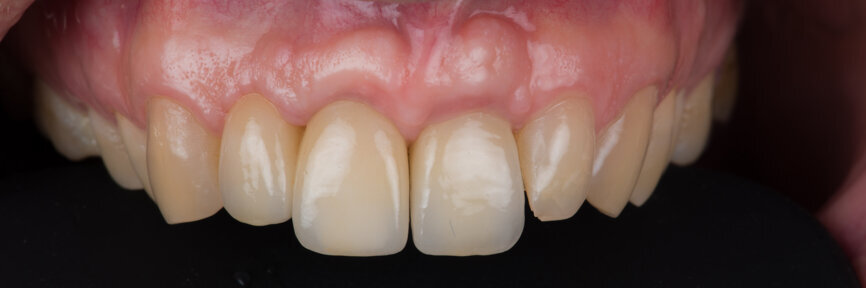

Prosthetic procedure

Two months after the extraction of tooth #12, an implant level impression was taken for final restoration using a digital scan body (Fig. 18) and a digital intra-oral scanner (TRIOS, 3Shape). A zirconia cantilevered fixed implant-supported bridge was fabricated according to a fully digital workflow (Figs. 19 & 20). The screw-retained bridge was then torqued to 35 N cm (Figs. 21 & 22). The follow-up, ten months after implant placement, showed a well-preserved gingival contour (Figs. 23 & 24).